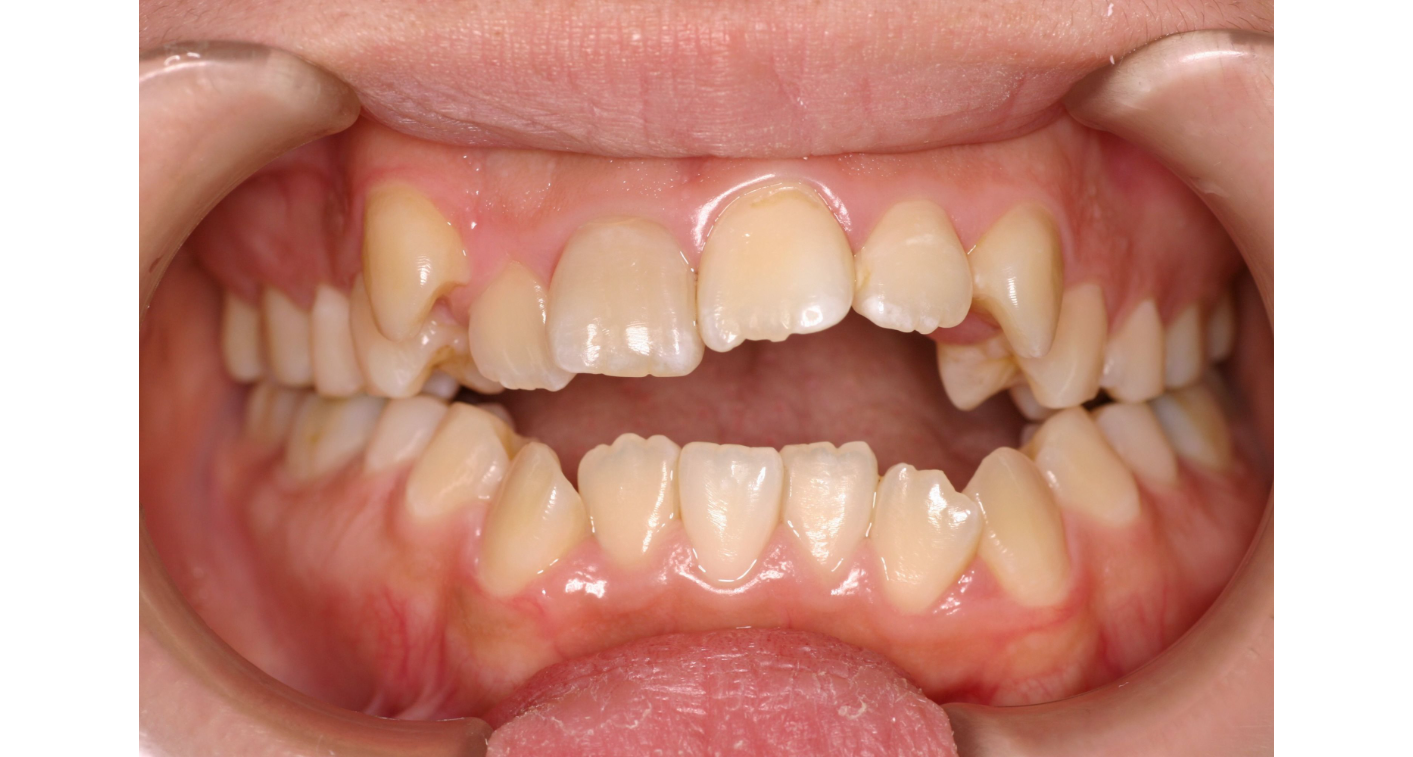

Before

主訴

前歯のすき間が気になる

治療内容

矯正装置は目立たないものをご希望されておりましたので、白いブラスチックの装置(ホワイトブラケット)に対して、金属のワイヤーを通して矯正治療を行いました。

上下左右の3番目までが、白いプラスチックの装置(ホワイトブラケット)となり、6番目以降の歯は金属の装置(メタルブラケット)を使用しました。

治療費

総額:1,270,500円(税込)

内訳(全て税込)

矯正相談料:1,100円

精密検査料:44,000円

矯正装置料:715,000円(ホワイト)

矯正調整料:159,500円(5500円×29回)

保定装置料:33,000円(上下)

治療期間

約2年半

通院回数

30回

想定されたリスク

・舌突出癖や口呼吸が残っていると、矯正後に再び開咬が戻る。

・治療期間の長期化